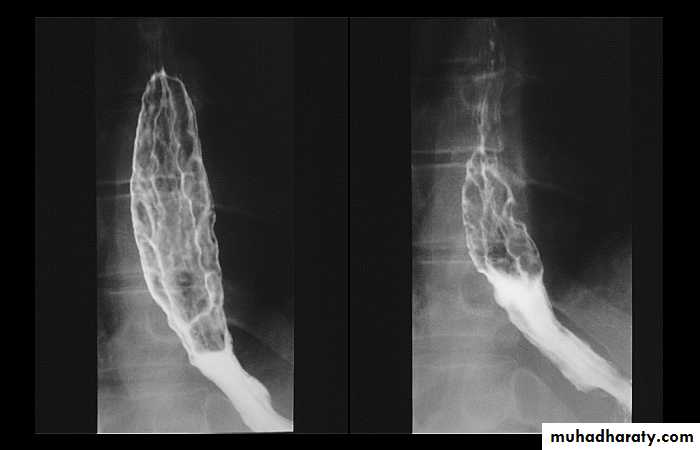

1-Dilatation of venous plexus in the wall of the esophagus due to increased pressure ( portal H.T.).

2-Important cause of Hematemesis .

3-Early changes seen in the mucosa (D.C.) loss of parallelism with thick and tortuous folds.

4-Later multiple small filling defects (fine cobble stone).

5-In advanced stage large filling defects ( coarse cobble stone ) .

6- More advanced stage elongated and worm like filling defect .

7-The changes are seen at lower third and gastric fundus.

Esophageal Varieces